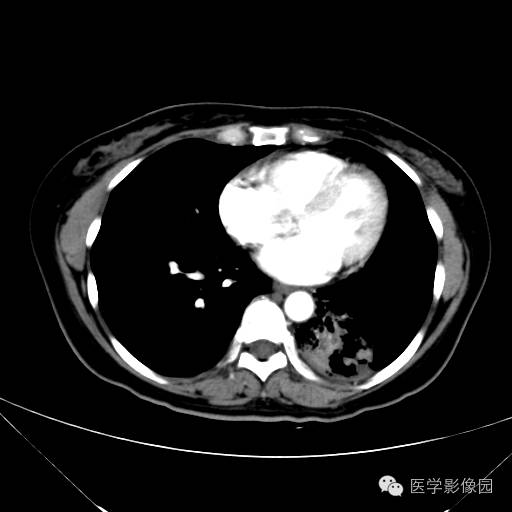

肺叶实变性支气管肺泡癌1例CT影像表现